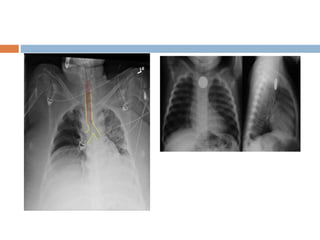

 Check for tubes, pacemaker, wires, lines foreign

 If an endotracheal tube is in place, check the

4cm above the carina

Endotracheal tube

 ETT tip 5 cm +/- 2 cm above carina

Central venous line

 Cv line tip in the superior vena cava or at the

cavo atrial junction i.e at the level of 1st

anterior intercostal space above carina

Intercostal tube

 ICD tip lies between visceral and parietal

pleura

 Anterosuperiorly to drain pneumothorax

 Posteroinferiorly to drain haemothorax

Pacemakers

 Single chamber – tip in right appendage or

right ventricular apex

 Dual chamber – tip in right atrium and right

ventricular apex

 Biventricular – tips in right atrium ,ventricle and

coronary sinus